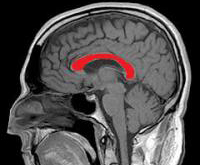

Мозолистое тело мозга — это толстые группы нервных волокон, соединяющие две половинки мозга друг с другом и обеспечивающие возможность быстрого обмена информацией между левым и правым полушариями. Они играют важную роль в восстановлении двигательных навыков после инсульта.

Исследование показало, что у пациентов, перенесших инсульт с особо тяжелыми нарушениями подвижности рук, канал связи между двумя полушариями мозга сильно поврежден.

Для того чтобы продемонстрировать структурные связи между областями мозга, ученые применили диффузную магнитно-резонансную томографию, которая может быть использована для отслеживания активности нервных волокон. ДМРТ основана на том принципе, что клеточные элементы, такие как мембраны, препятствуют распространению молекул воды, предотвращая их от случайно дифференциации. Следовательно, параллельно нервные волокна можно визуализировать довольно четко. У пациентов после инсульта был занижен уровень диффузии в области мозолистого тела. То есть, инсульт повредил эти связи.

Инсульт не только повреждает клетки в очаге ишемии, но и влияет на отдаленные структурные связи, мешая пациентам восстанавливать моторные функции. Сейчас ученые изучают возможность восстановления связей между полушариями мозга за счет ранней стимуляции.